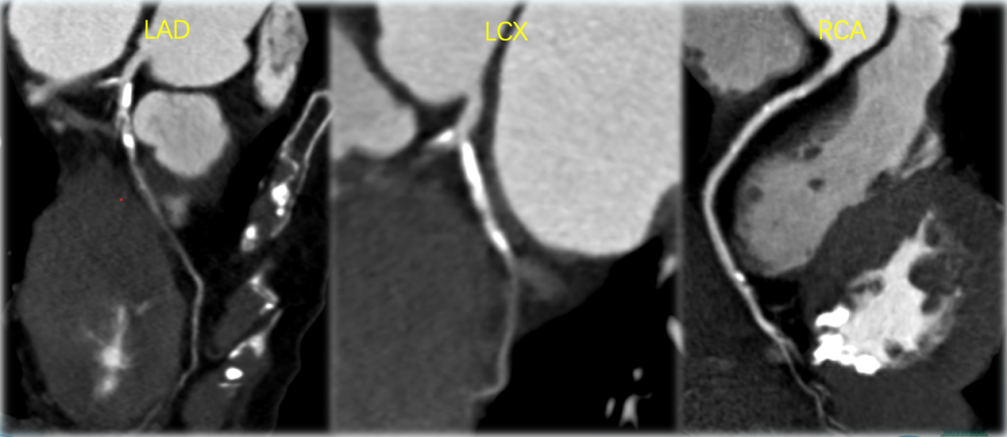

CT冠脉评估患者三支主干未见严重狭窄。前降支近段存在一30%狭窄的钙化斑块,右冠细小,为左优势型冠脉。

CT冠脉评估显示其前降支和回旋支重度狭窄;进一步造影评估后,于前降支近中段植入 3.0*30mm Resolute 支架。

CT冠脉评估

造影证实前降支和回旋支重度狭窄